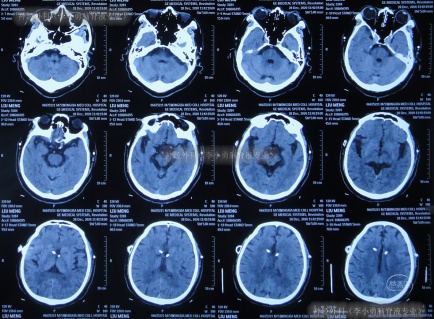

但出院后1个月即2020年12月6日(脑室腹腔分流术后3年零2月),再次出现嗜睡,第3次就诊该院,查头颅CT(片子丢失)后认为脑室系统与1月前相比并未明显扩张,但第2天即2020年12月7日,出现昏迷,大小便失禁,再查头颅CT(图-3)后认为脑室有大。

图-3:2020年12月7日头颅CT